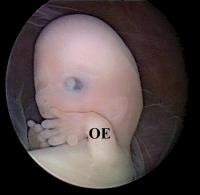

GD1-Embryo

Abbildung 3: Embryoskopische Darstellung eines leeren Fruchtsacks (GD1-Embryo). Die Embryonalanlage fehlt. Das Amnion (A) ist direkt am Chorion (C) adhaerent. Die Schwangerschaft resultierte nach IVF. Ein abnormer Karyotyp (45,X) wurde zytogenetisch diagnostiziert.